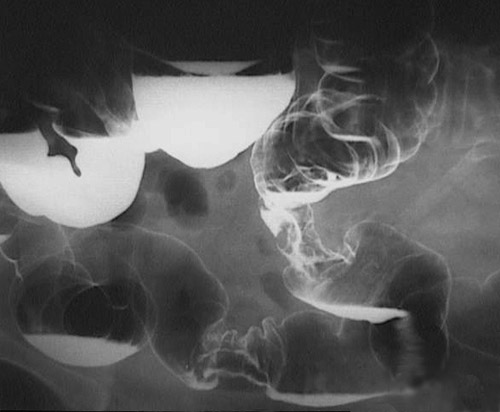

This barium enema with the patient in a lateral position (head toward the right of the image) demonstrates two encircling masses, one in the

transverse colon

and one in the

descending colon

. These are typical adenocarcinomas.